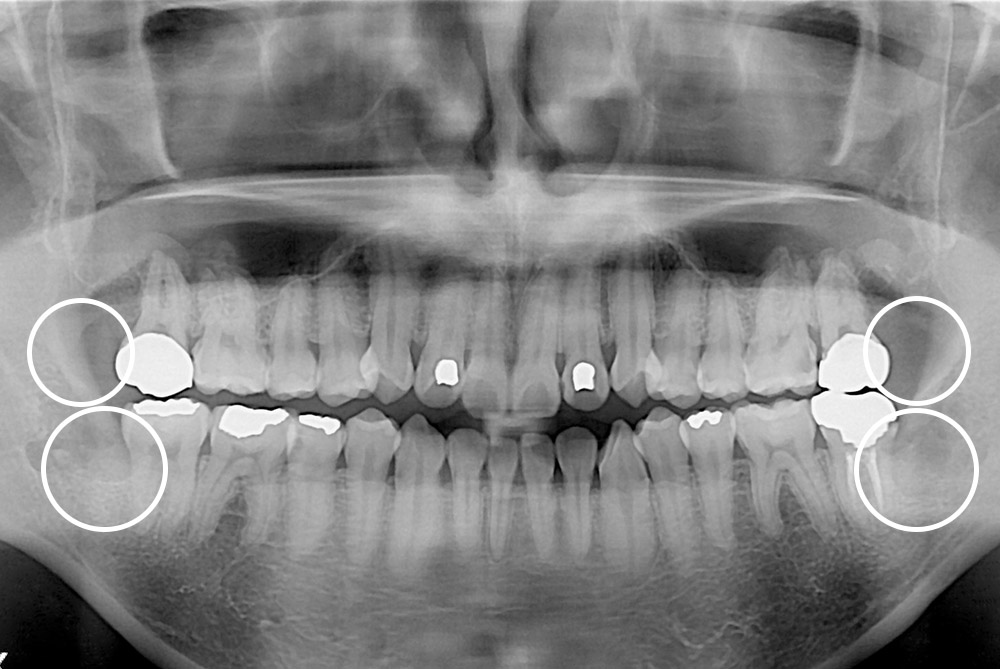

[사랑니] 매복 사랑니 발치

치료후 : 2018-10-20